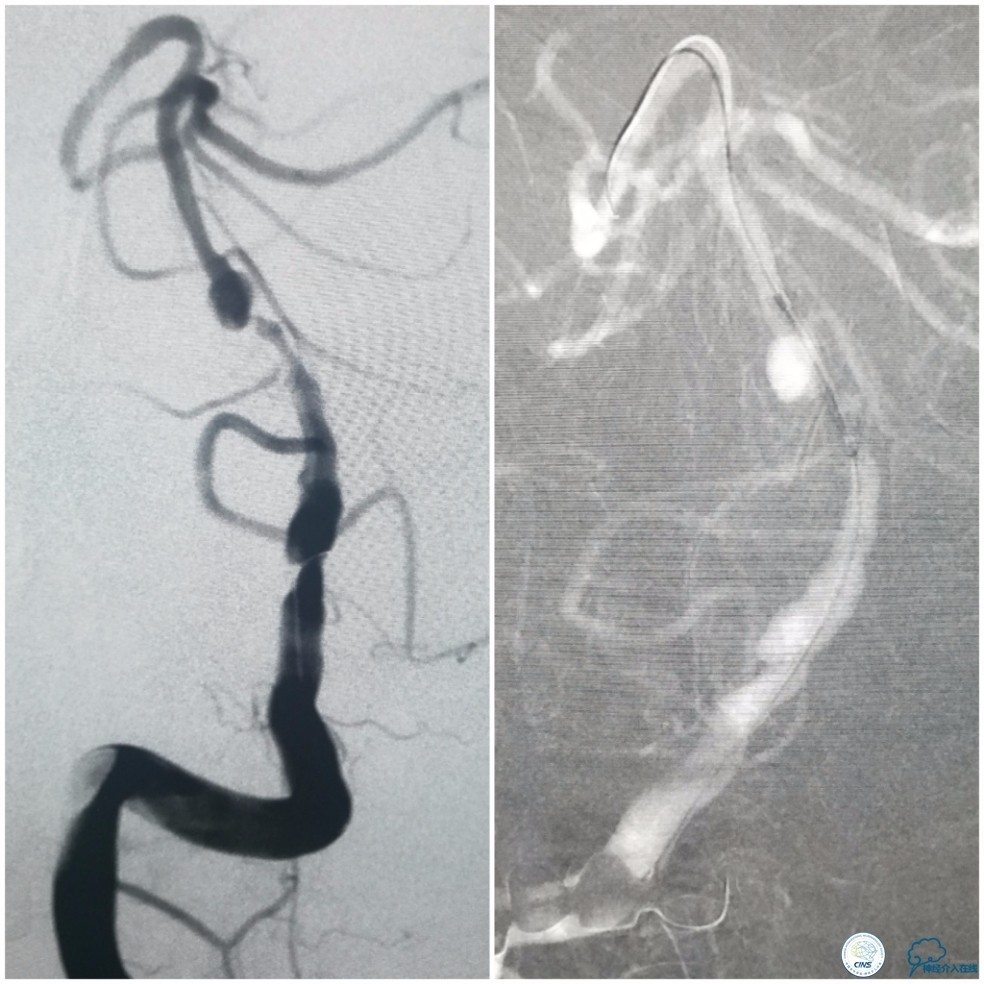

术前DSA:基底动脉中段狭窄,狭窄远端动脉瘤,右椎动脉优势,右椎V4段管壁不光滑(图7)。

图7

左椎动脉V3段以远未见显影(图8)。

图8

前循环未见明显向后循环代偿(图9)。

图9